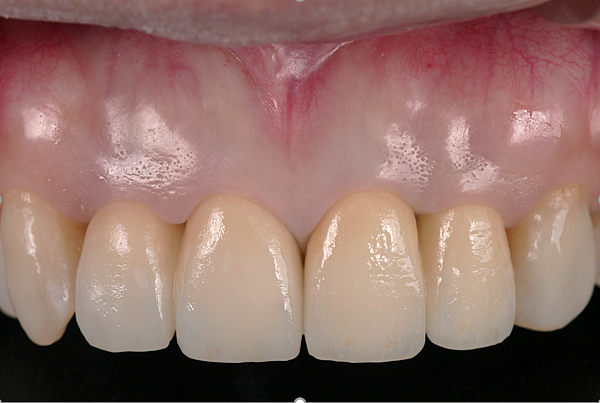

前牙審美全瓷冠